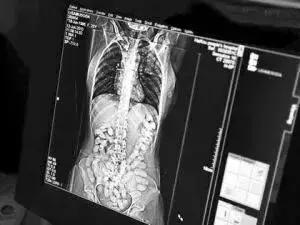

CT显示下的腹内藏毒